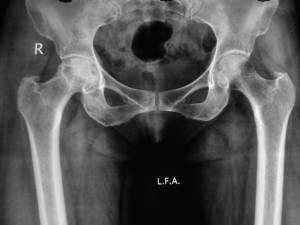

166) A 42 year old woman with history of lupus nephritis presents with complaints of pain in her right thigh. Pain increases on walking and standing. Her kidney disease is under control on Prednisone maintenance for past one year. She denies any recent trauma. On physical examination, she is noted to have a right sided limp on walking. Her Hip X-ray is shown below:

The most likely etiology for the condition shown above:

E) Prednisone therapy

It is avascular necrosis with fracture neck of femur Rt.